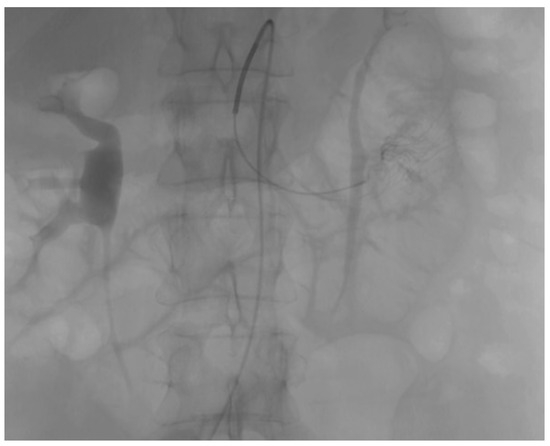

| Day 0—H23:30 | Angiography | Active contrast extravasation from ileocolic branches → selective embolization performed. |